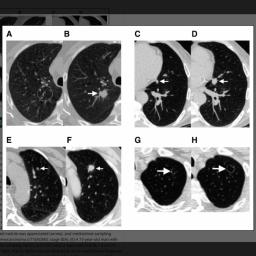

Studie: Deep-Learning-Modell "Sybil" soll bei Lungenkrebsfrüherkennung helfen

Mit dem Deep-Learning-Model "Sybil" ist es Forschern gelungen, das Lungenkrebsrisiko bis zu sechs Jahre vor der Erkrankung anhand eines CT-Scans zu bestimmen.